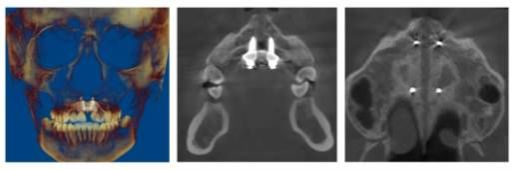

▲图丨扩弓完成后,腭中缝打开,上颌骨狭窄改善

上颌牙弓狭窄、横向宽度发育不足是常见错畸形问题,在南疆因呼吸道疾病高发呈发病率上升趋势。儿童青少年可通过传统扩弓器改善,但14岁后传统方式效果锐减,成人上颌扩弓曾几乎只能依赖外科手术,且扩弓量受骨裂隙区愈合能力限制。而口腔医院改进优化并申请专利的上颌骨骨性扩弓器(MSE)技术,通过植入4颗大直径、高强度微种植支抗钉,穿通上颌骨腭旁区骨皮质,传递螺旋扩弓器矫形力,精准扩大腭中缝,为青春发育期后及腭中缝闭合的成人患者提供了微创解决方案。